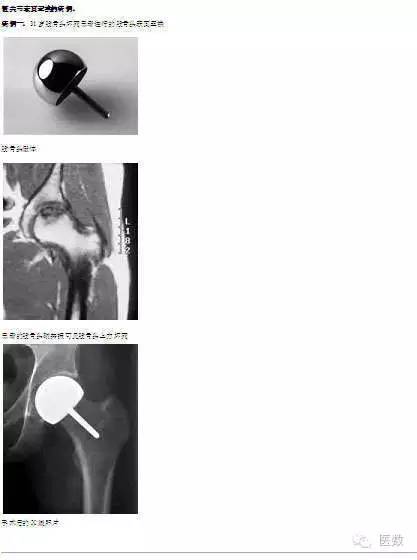

传统的全髋关节置换治疗髋部骨折、股骨头坏死和骨关节炎等疗效肯定,目前全世界每年有上百万病人进行此类手术。但由于全髋关节置换的假体有一定的使用寿命(15-20年不等),而且假体磨损产生颗粒造成的骨溶解、假体磨损、假体安装后由于应力传导改变导致的疼痛等因素严重影响了全髋关节置换的应用。相对于传统的髋关节表面置换,髋关节表面置换保留了大部分的股骨头和股骨颈,即保留了大部分的骨质,为病人的再次翻修手术留下了极大的余地,尤其适合于年轻病人的髋部疾病。当前的表面置换使用金属对金属假体,延长了假体寿命,同时减少了聚乙烯颗粒的产生。

1.保留了大部分股骨头,无须处理股骨髓腔,为翻修手术保留了足够的骨质。

2.假体直径较大,减少了术后脱位的发生率。

3.保持了股骨正常的应力传导,减少了由于应力传递改变引起的全髋关节置换术后大腿疼痛。

4.使用金属假体,避免了由于使用塑料假体(聚乙烯)产生磨损颗粒而导致的假体晚期松动。

5.金属假体更为耐磨,使假体使用寿命增加。